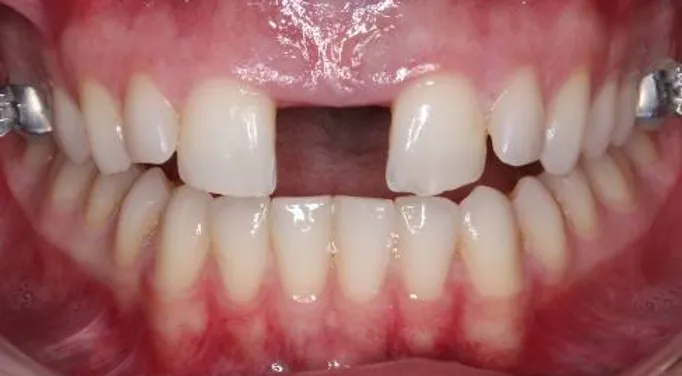

if you have bad transverse maxillary deficiency then definitely look into it. i want to try and get this however i dont know if i'll be eligible seeing as how my lower arch is like 10mm smaller than my maxillary arch.

look how the maxilla was ripped apart on this one holy chit